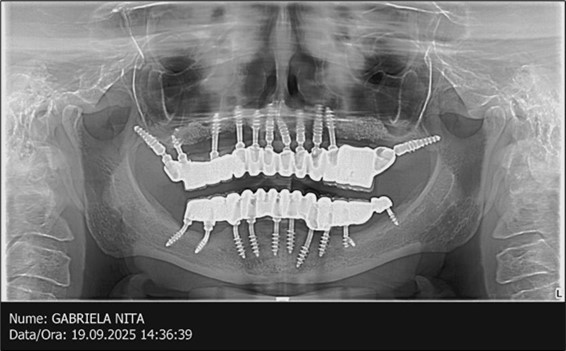

The results of rehabilitation treatment with corticobasal and compressive implants with a polished surface after the failure of two stage implants were highlighted over a period of 3 years and 3 months as being very good (Figure 14, Figure 15), with the patient completing a satisfaction survey in this regard. Certainly, it is necessary to continuemonitoring these results in the long term.

Figure 14.Rx panoramic final situation control: (a) Panoramic X-ray with the addition of a distal BCS implant in quadrant 3 at 11.2022; (b) Control X-ray, 10.2023.